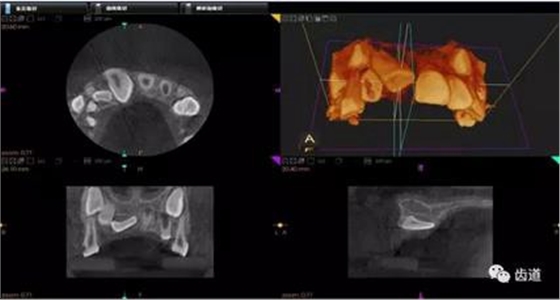

1、上頜尖牙阻生

上頜尖牙埋伏阻生在CBCT中的影像